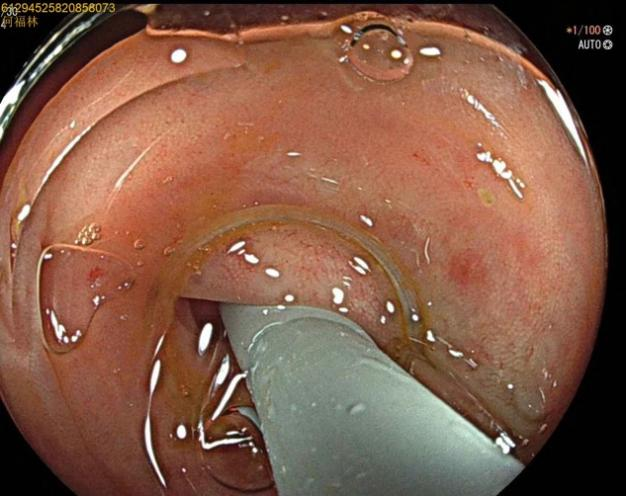

52岁,女性患者,主因“反复右下腹痛1年,再发2天”入院,既往有急性阑尾炎发作病史,入院腹部查体:右下腹麦氏点明显压痛,无肌紧张及反跳痛;完善腹部+盆腔CT示:阑尾管腔增粗并阑尾粪石形成,周围多发淋巴结显示。结合患者的病史及检查考虑慢性阑尾炎急性发作。次日,行肠镜检查,进至阑尾口,置入子镜(洞察内镜)进入阑尾,见阑尾黏膜充血、水肿,附着有白色絮状分泌物,确诊急性阑尾炎发作,进一步行内镜下逆行性阑尾治疗术,术中给予阑尾腔冲洗后植入塑料支架,术后患者腹痛即可缓解。